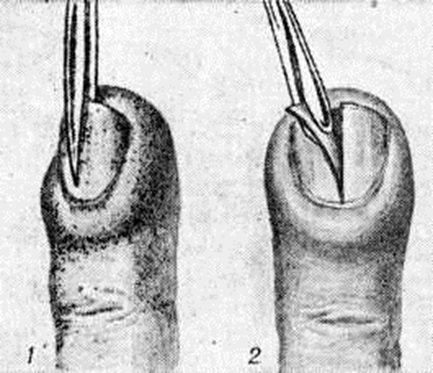

Лечение подногтевого Панариций только оперативное. При расположении гноя вблизи свободного края тела ногтя ногтевую пластинку иссекают под местной анестезией в виде клина. Часто в таких случаях обнаруживается инородное тело — заноза, явившаяся причиной Панариций Полностью удаляют ноготь (рисунок 10) только при отслойке его гноем на большом протяжении.